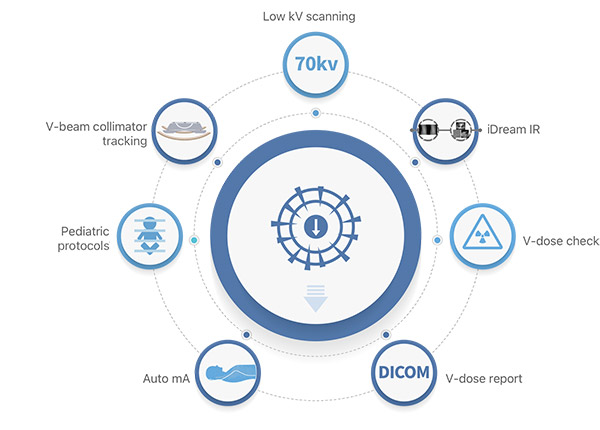

- Лучевая нагрузка — особенно важно для скрининговых программ;

Компьютерные томографы SinoVision – продукция китайской компании SinoVision Technologies (Beijing) Co., Ltd. Компания была основана в 2012 году и на сегодняшний день является лидером КНР в этой сфере. КТ SinoVision применяются для проведения рутинных исследований, диагностики в онкологии, кардиологии, КТ-радиологии, ветеринарии. Их отличают высокая точность и низкая лучевая нагрузка. Кроме того, стоимость томографов SinoVision ниже, чем западных и европейских аналогов, а на их техническое обслуживание и ремонт не влияют внешние ограничения.

Компьютерные томографы SinoVision обеспечивают удобное размещение пациентов, превосходную визуализацию структур, включая мелкие сосуды, и низкую лучевую нагрузку.

- Минимизация лучевой нагрузки до 63%